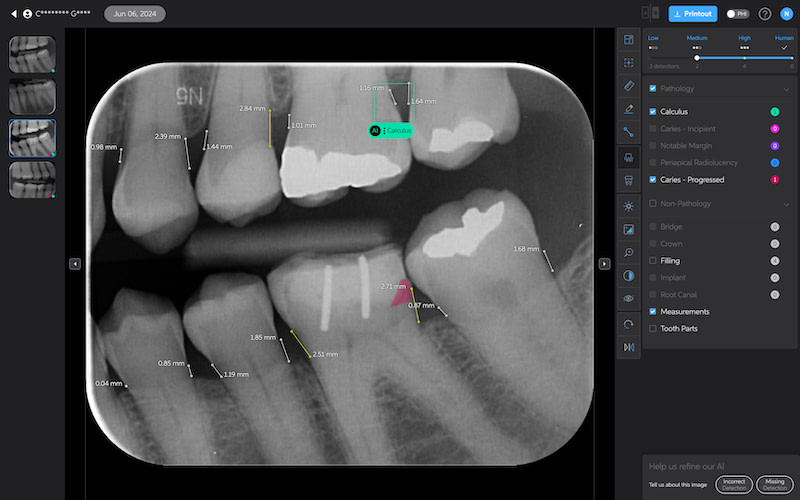

Bone Measurements

The system provides automated measurements from the crest of the bone to the cementoenamel junction (CEJ). These measurements are color-coded to indicate severity:

- White: 0-2.5 mm

- Yellow: 2.5-4 mm

- Amber: >4 mm

This feature is helpful for periodontal assessments, streamlining the process of identifying areas of bone loss. However, it's important to note that image angulation can affect the accuracy of these measurements, a limitation the system acknowledges.

I found these lines to be incredibly useful when describing patients' periodontal health. Cool feature, no doubt.

Calculus Detection

Green squares highlight areas of radiographic calculus. This tool is useful for hygienists and dentists in treatment planning and patient education.

Quite self-explanatory and the system didn't seem to miss often, if ever.

Notable Margins

Purple squares indicate areas of notable margins, such as potential overhangs or open margins on existing restorations.

This is particularly useful as well. I find that patients hate hearing that there is secondary decay at the edge of a crown, for example. And it is always a touchy subject if it is a recent crown done elsewhere. With AI, you are effectively removing yourself and any perceived sales bias from the diagnosis. This is what the AI shows.

Sometimes AI doesn’t get it right.

AI is just a tool, and those who think it will get it right and 100% correct each time are thinking of this in the wrong way.

I view Pearl and Second Opinion as a method to standardize diagnosis, educate, and, most importantly, to function as a patient communication tool.

Sometimes, AI does not get it right and does not pick up anything. Or sometimes the detection is wrong, and you should only use it to focus your attention on potentially crucial areas but still make a call yourself.

Here are some things I noticed AI missed or picked up incorrectly:

- It detects a ‘notable margin’ on an implant crown that is just the abutment-crown joint.

- Or calls a natural tooth an implant

- Or misses the apparent secondary decay under a PFM

- Seems to be less sensitive to widening of the PDL, rarely picking it up.

- It denoted leftover resin cement around a crown as calculus

- Does not seem to pick up resorbed roots

But overall, it is still impressive. Of course, AI does not have ‘bad days’, tiredness, or fatigue. It reports things the same way each time. It also gets better with time, one would hope.